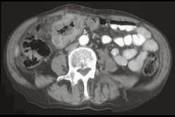

问题 男,45岁,右下腹胀痛、并可触及质硬包块,请结合图像选择最可能诊断 ( )

选项 A.结肠Crohn氏病 B.结肠癌 C.肠结核 D.结肠淋巴瘤 E.慢性溃疡性结肠炎

答案 B